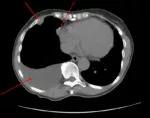

<p>Computed tomography image at the time of the patient's diagnosis in 2017. Arrows at top show mesothelioma tumors. Lower arrow indicates pleural effusion.</p>

A 63-year-old woman with prior secondary asbestos exposure was referred to Cleveland Clinic with discomfort in her chest and upper abdomen. Suspicious findings, including right-sided pleural effusion and thickening of the pleura around the effusion, had been detected on chest X-ray, CT scan and PET scan. After further workup, she was diagnosed with epithelioid mesothelioma of her right pleura.